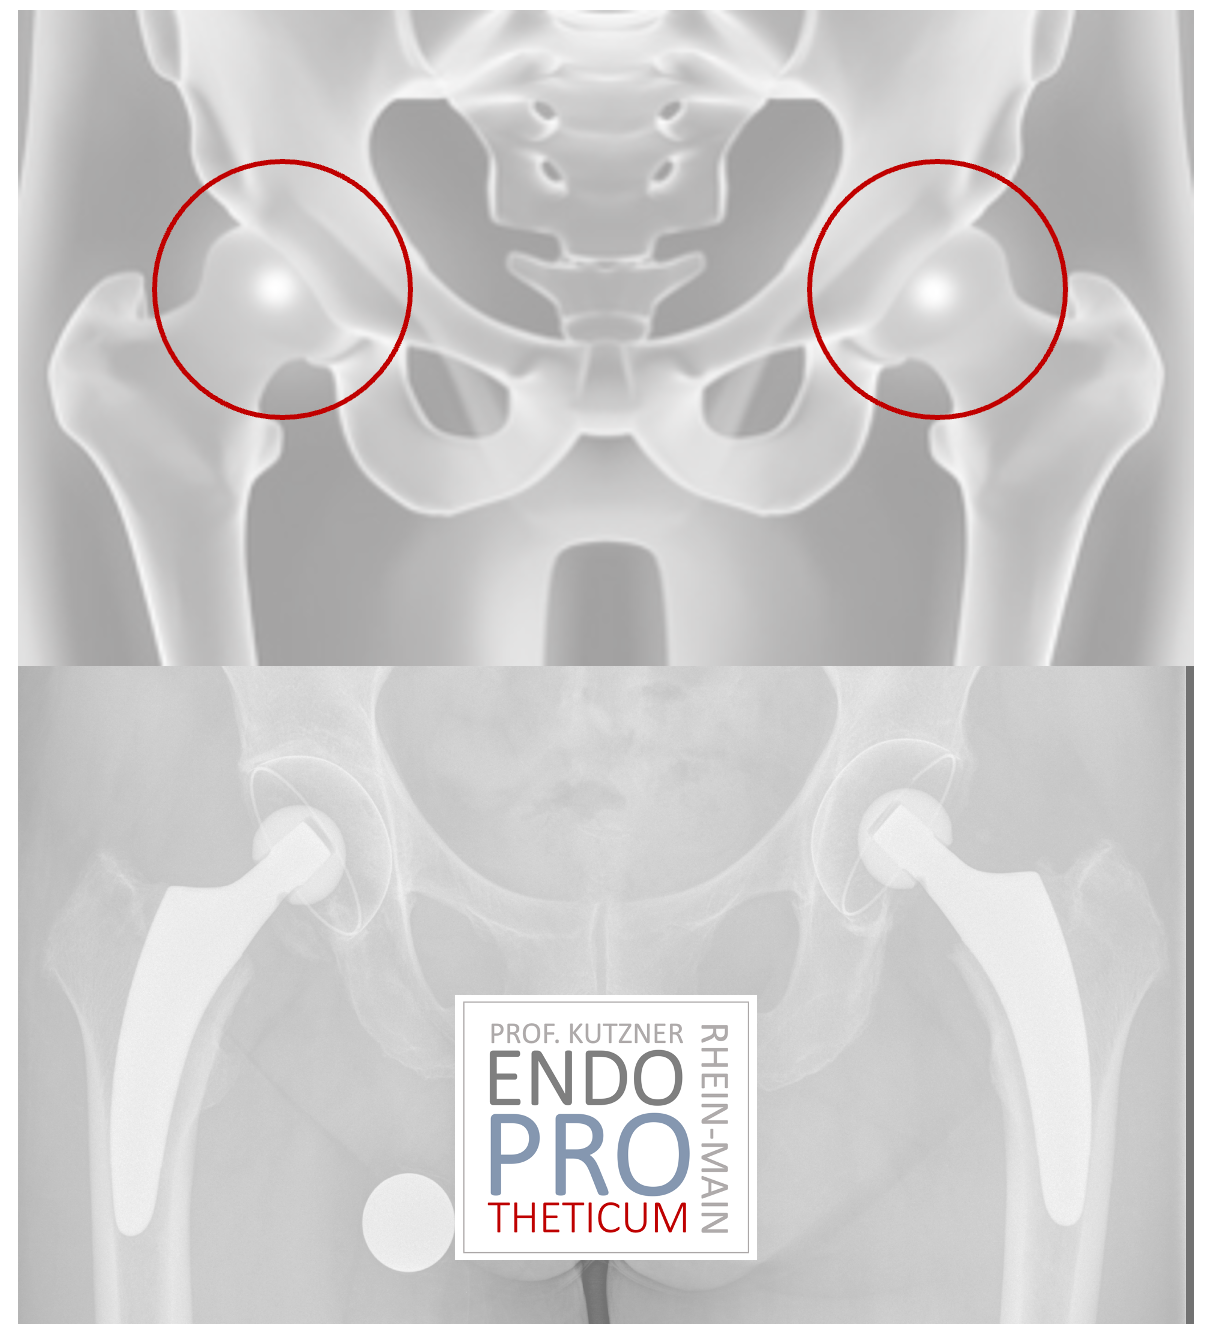

Short-stem prostheses have become increasingly popular in recent years. The implantation of a short-stem PROSTHESIS aims to preserve the bone and create favorable conditions for revision without changing the basic concepts of conventional hip arthroplasty.

The concept of modern calcar-guided short stems in hip arthroplasty aims at the precise reconstruction of the individual, anatomical hip geometry. A bone and soft tissue-sparing implantation technique is used in conjunction with a physiological load in the part of the femur near the joint in order to preserve the bone in the long term.